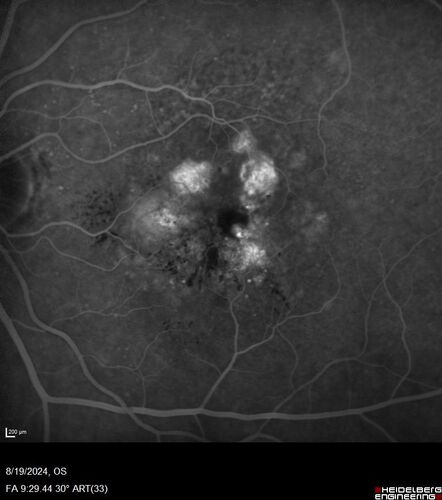

Wet AMD - Occult CNVM and Geographic atrophy

77 year old female with mild vision loss - 20/32 - responded to Avastin

Occult CNVM wet AMD and Geographic Atrophy